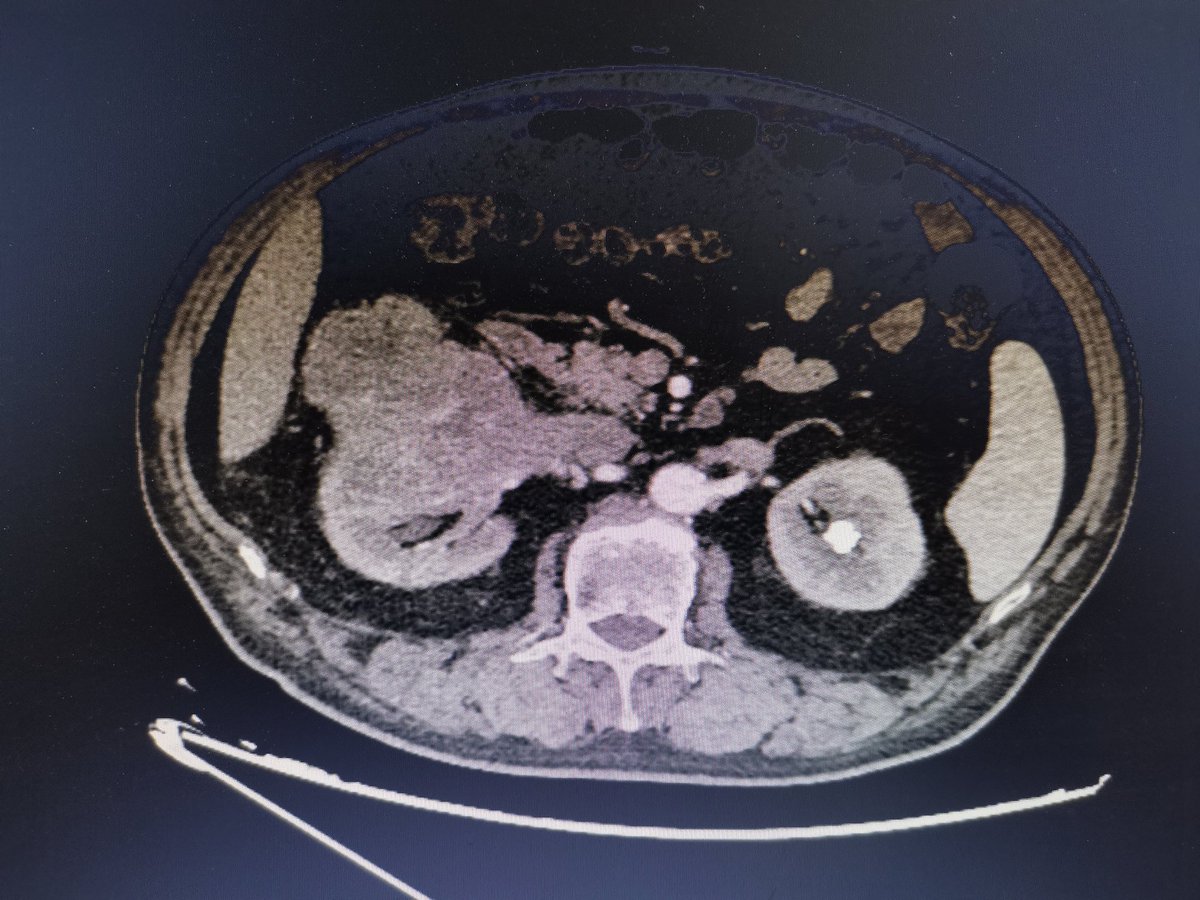

Ultrasound guided percutaneous renal access - Module 3: trainning in the GPHANTOM KIDNEY developed by @BatagelloUro, @VicentiniUro and @gphantomBR. That’s a realistic phantom based on CT scan 3D reconstruction of the human kidney. Really appreciate @Sonosite @hospitalHCFMUSP